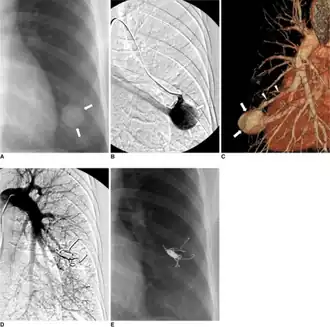

Treatment

Treatment for brain AVMs can be symptomatic, and patients should be followed by a neurologist for any seizures, headaches, or focal neurologic deficits. AVM-specific treatment may also involve endovascular embolization, neurosurgery or radiosurgery.[6] Embolization, that is, cutting off the blood supply to the AVM with coils, particles, acrylates, or polymers introduced by a radiographically guided catheter, may be used in addition to neurosurgery or radiosurgery, but is rarely successful in isolation except in smaller AVMs.[22] Gamma knife may also be used.[23]

Treatment of lung AVMs is typically performed with endovascular embolization alone, which is considered the standard of care. [24]